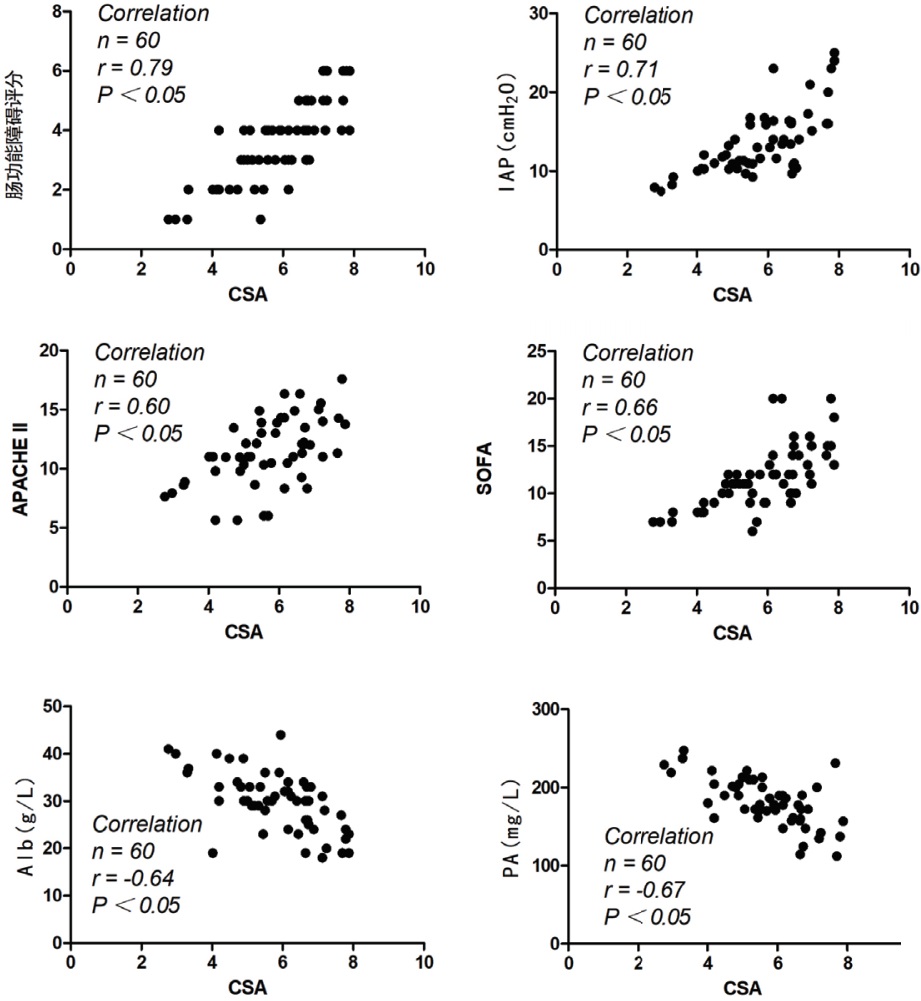

2.6 CSA与其他胃肠功能障碍指标的相关性分析对30例超声治疗组患者入院当天与第5天的CSA与胃肠功能障碍评分、APACHEⅡ评分、SOFA评分、IAP、PA、Alb进行相关性分析,CSA与各项指标均具有相关性,且与胃肠功能障碍评分、APACHEⅡ评分、SOFA评分、IAP呈正相关,相关系数分别为0.79、0.60、0.66、0.71,与PA、Alb呈负相关,相关系数分别为-0.67和-0.64,P均<0.05,见图 2。

| 图 2 CSA与其他胃肠功能障碍指标的相关性分析 Fig 2 Correlation analysis of CSA and other indicators of gastrointestinal dysfunction |

本研究立足于以上理论指导,采用床旁超声测量胃窦横截面积来指导脓毒症患者的早期个体化肠内营养方案的制定实施。结果发现,经床旁超声连续监测患者胃肠功能,能够在较早期地发现患者的喂养不耐受情况,超声治疗组在第1天发现喂养不耐受的发生率(36.67%)显著高于常规治疗组(10.00%),并制定个体化的治疗方案,入院第3天超声治疗组的喂养不耐受发生率仅为10.00%,显著低于常规治疗组(40.00%)。治疗至第5天,超声治疗组的相关功能评分、营养状态指标及炎症相关指标等较入院时均显著改善,且显著优于常规治疗组,另外超声治疗组患者的ICU住院天数及误吸发生率更低。各项指标均提示床旁超声测量CSA指导脓毒症患者的早期个体化肠内营养方案实施的有效性。为进一步探究CSA对喂养不耐受的预测价值,首先对CSA与传统功能评分系统及指标进行了相关性分析,其相关系数的绝对值均在0.6以上,其中与胃肠功能障碍评分、腹内压的相关性高达0.79、0.71。接着ROC曲线也显示CSA预测喂养不耐受的AUC为0.828,其敏感度和特异度分别为88.20%和71.80%,其预测的Cut off值为7.835 cm2。虽然其敏感度高达90%左右,但其特异度为70.00%左右,阴性排除率相对偏低,这也提示我们可能需要结合患者临床表现综合评定。